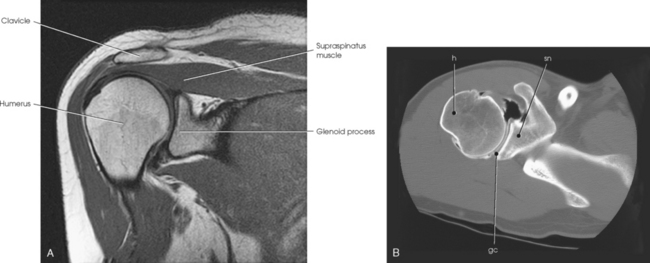

The scapulohumeral articulation between the glenoid cavity and the head of the humerus forms a synovial ball-and-socket joint, allowing movement in all directions (Figs. 5-9 and 5-10). This joint is often referred to as the glenohumeral joint. Although many muscles connect with, support, and enter into the function of the shoulder joint, radiographers are chiefly concerned with the insertion points of the short rotator cuff muscles (Fig. 5-11). The insertion points of these muscles—the subscapular, supraspinatus, infraspinatus, and teres minor—have already been described.

Fig. 5-10 A, Coronal MRI of shoulder. Note articular cartilage around humeral head and muscles closely surrounding bone. B, Axial CT of shoulder, mid-joint. Note position of bones relative to each other and articular cartilage in glenoid cavity. gc, glenoid cavity; h, humerus; sn, scapular neck. (From Kelley LL, Petersen CM: Sectional anatomy for imaging professionals, ed 2, St Louis, 2007, Mosby.)